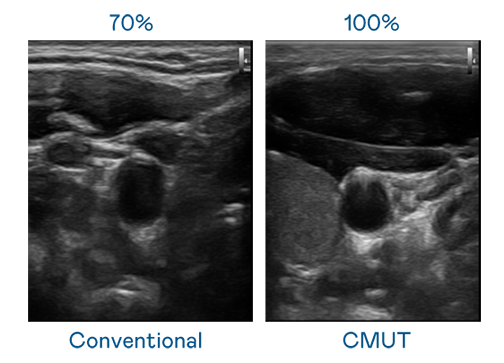

CMUT 技术是一种用电容式微机电元件来产生超音波讯号的技术。与传统 PZT 压电式技术相比,CMUT 频宽增加 30%,更宽频的超音波讯号让影像解析度大幅提升,是实现高影像品质医疗超音波扫描、促进精准医疗发展的关键技术。

大频宽带来超清晰影像

超音波影像的解析度高低,首先取决于探头能发出的讯号频宽。创世红海 CMUT 可提供高清晰的超音波讯号,提供高频宽、高灵敏度、影像纹理细节更高的超音波影像,协助医护人员缩短影像判读时间及利用精准的医疗影像进行诊断。